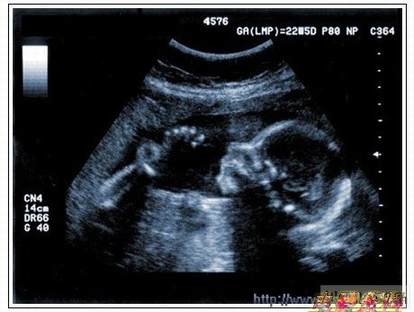

通过发射超声能量进入人体,接收并处理返回的反射信号,相控阵超声系统可以生成体内器官和结构的图像,映射血液流动和组织运动,同时提供高准确度的血流速度信息。传统设计中,构建这样的成像系统需要大量的高性能相控阵发射器和接收器,使得车载设备体积庞大且价格昂贵。近年来,随着集成工艺的进步,设计人员能够获得小尺寸、低成本而且高度便携的成像系统方案,并可达到接近大型成像设备的性能指标。而新的设计挑战依然存在,即在进一步提高方案集成度的同时提高系统性能和诊断能力。